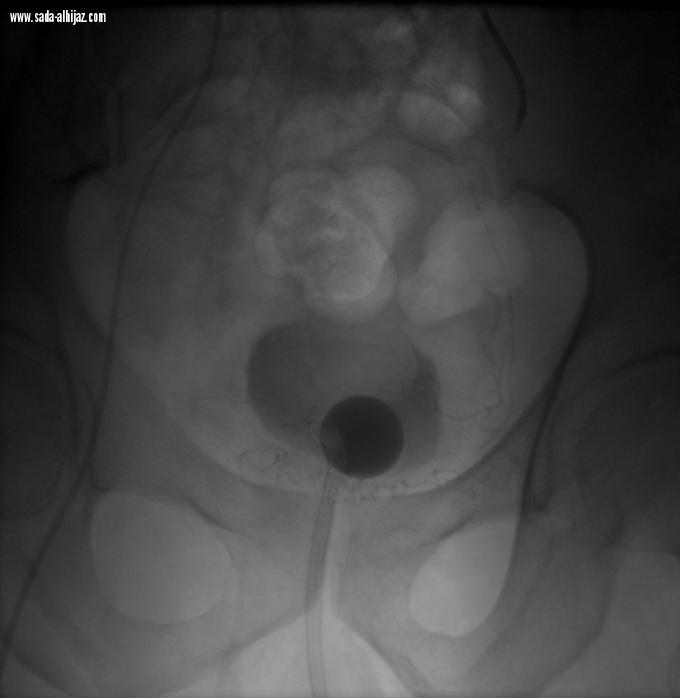

نجح بفضل الله فريق وحدة الأشعة التداخلية بمستشفى النور التخصصي بمكة المكرمة بالتعاون مع قسم جراحة المسالك البولية في إدخال خدمة جديدة و هي علاج تضخم البروستات الحميد المؤدي إلى إحتباس البول عن طريق الأشعة التداخلية.

وأبانت صحة مكة المكرمة بأنه تم تقديم هذه الخدمة لمريض سبعيني يعاني من إحتباس البول المزمن بسبب تضخم البروستات الحميد و عدم الاستجابة للأدوية و الإعتماد الكلي على قسطرة البول.

و نظراً لحالة المريض الصحية و التي تجعل من الجراحة التقليدية إجراء عالي الخطورة فقد تم تحويل المريض لأطباء وحدة الأشعة التداخلية و الذين قاموا بمعاينة المريض و مراجعة الفحوصات و عمل الأشعات اللازمة و من ثم اجراء العملية التداخلية بإستخدام التخدير الموضعي فقط .

وأضافت بأنه عند متابعة المريض على مدار الأشهر التالية فقد تحسن فيها إحتباس البول بشكل كبير و تمت إزالة قسطرة البول بشكل نهائي.

تجدر الإشارة أن هذا الإجراء الطبي يعتبر أحد الاجراءات الطبية الحديثة و المثبتة علميا بمنفعتها لمثل هؤلاء المرضى